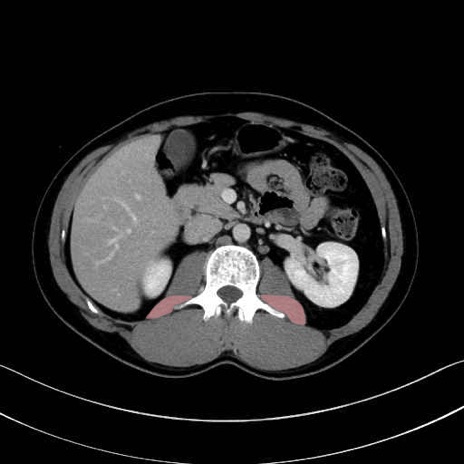

腰方形筋 (Quadratus lumborum)